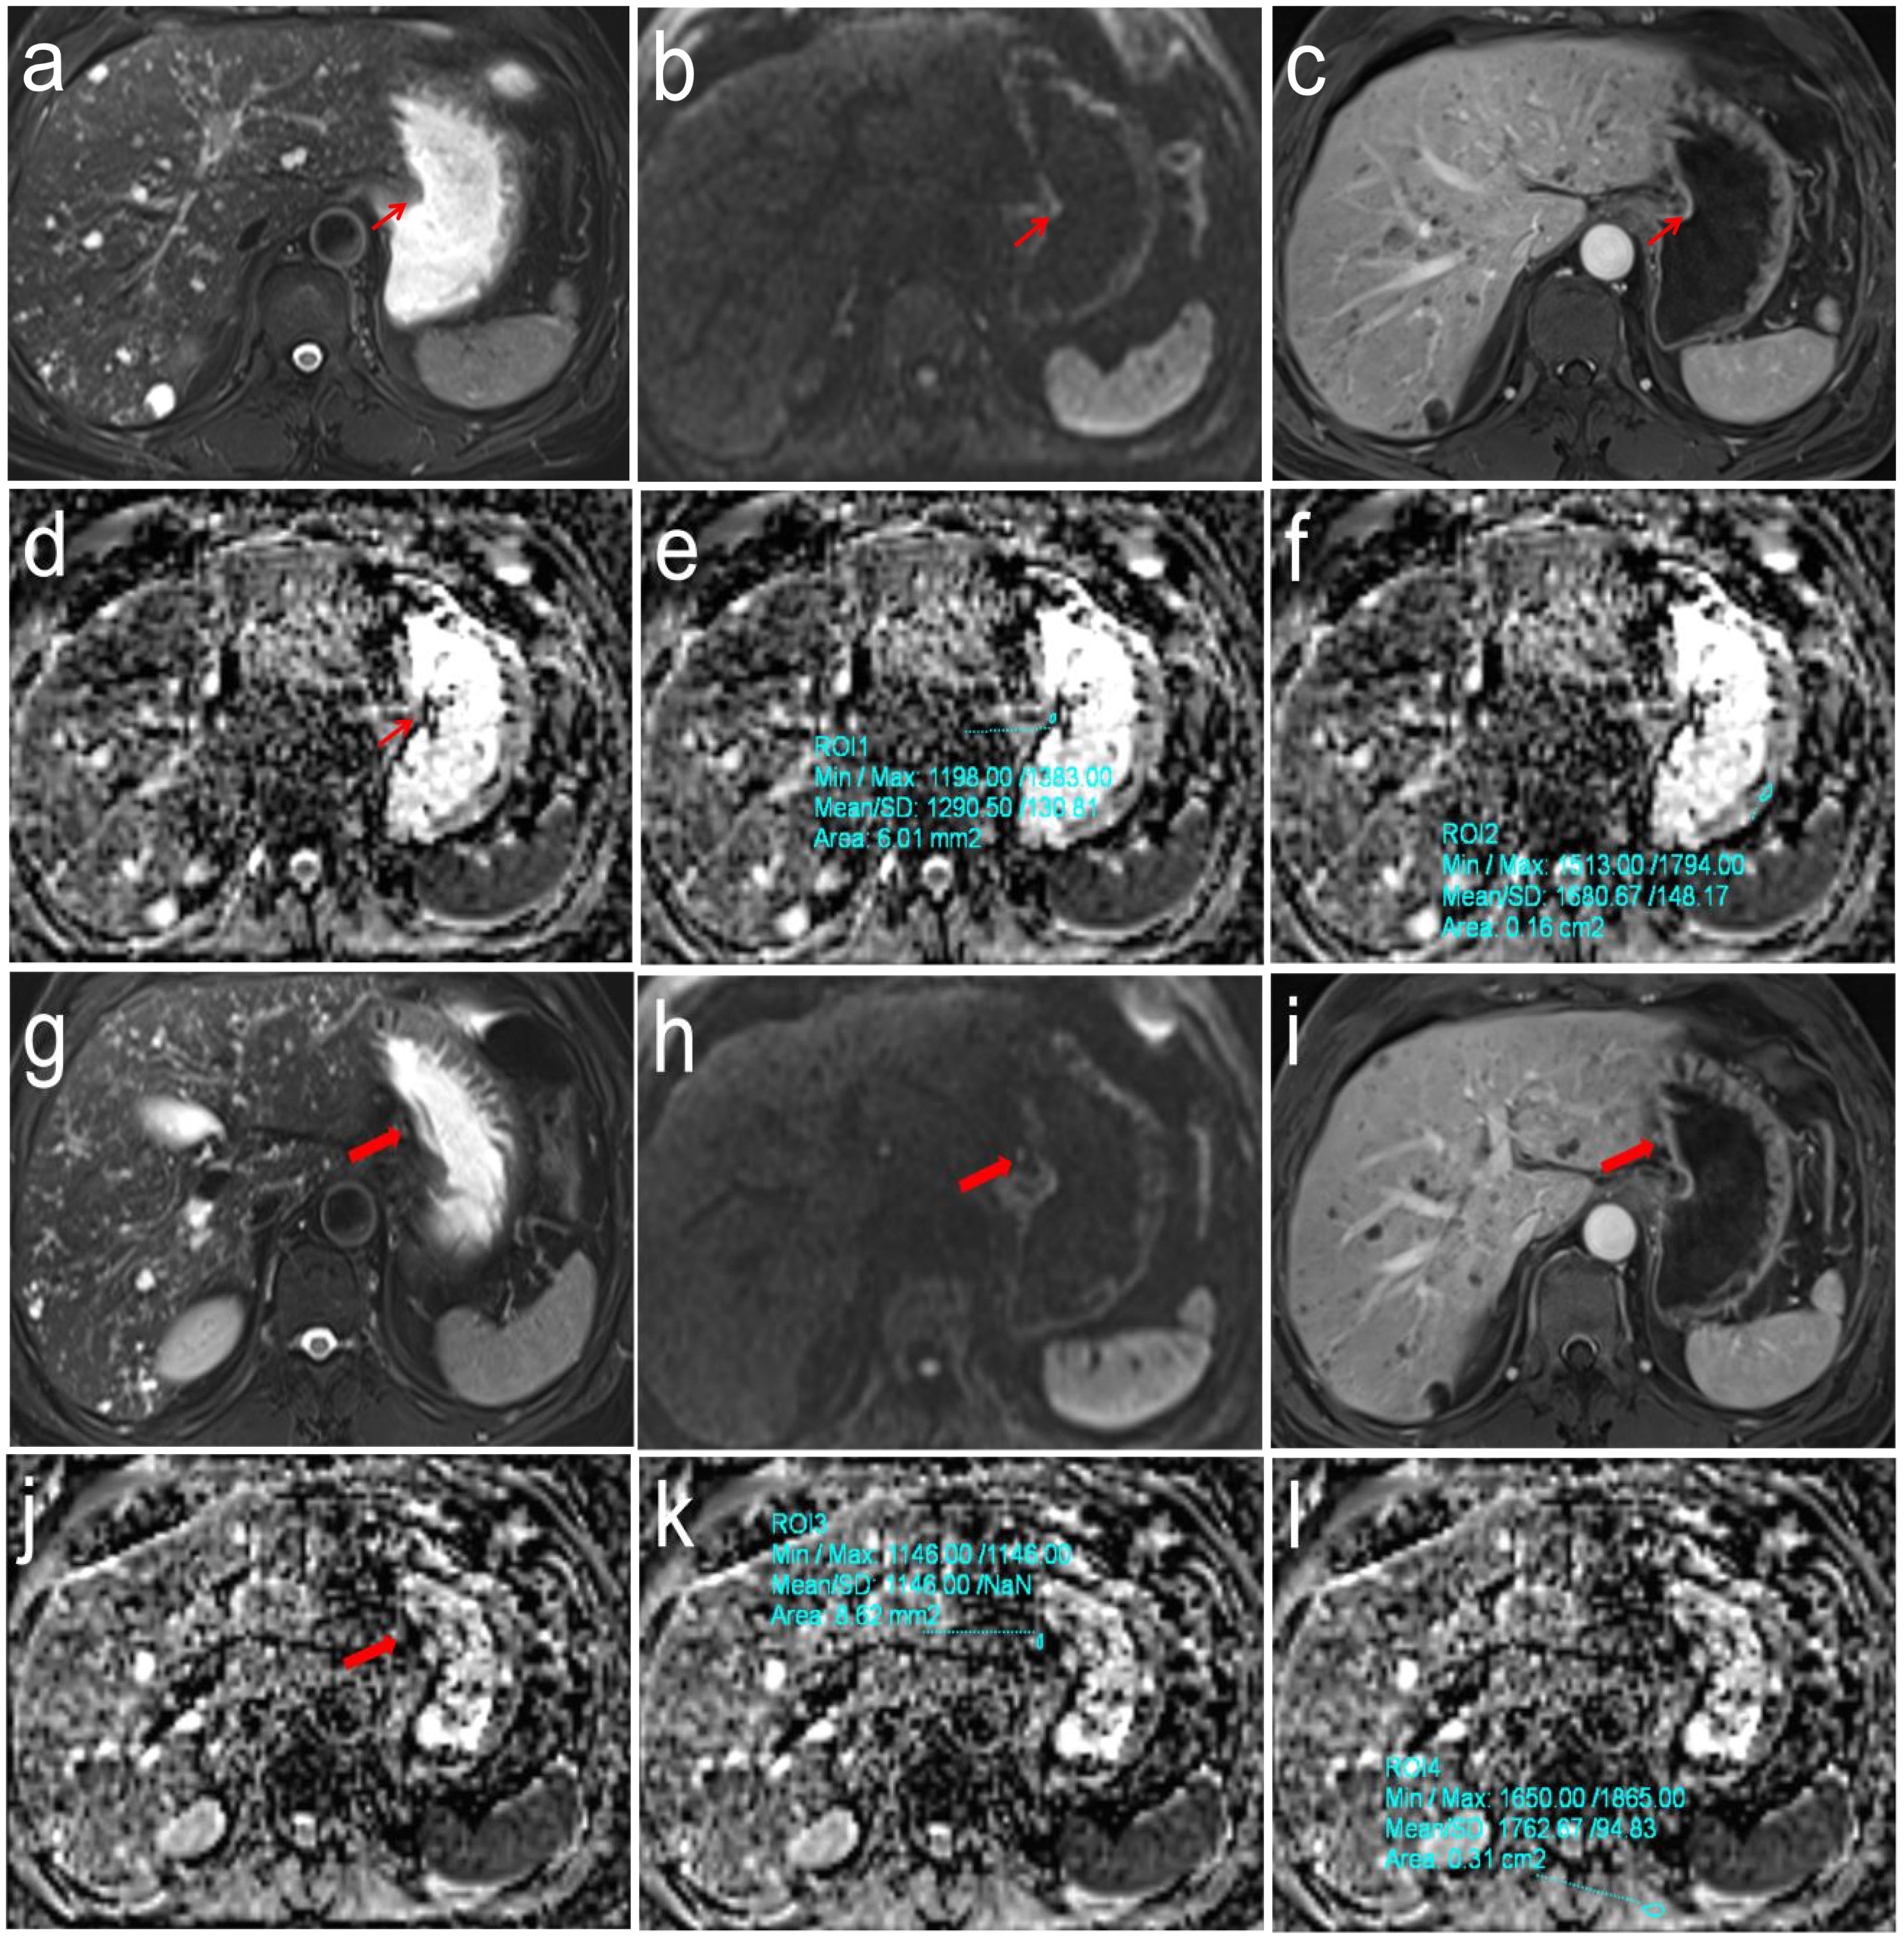

Purpose: To explore the differences in apparent diffusion coefficient (ADC) values based on the primary tumor and sentinel lymph node (SLN) for predicting N stages of gastric cancer (GC). Methods: One hundred and sixty histopathologically confirmed GC patients between April 2021 and October 2024 were prospectively recruited. Preoperative DW-MRI was performed, and ADC values from primary tumors (ADCT) and SLNs (ADCLN), along with their relative ratios (rADCT, rADCLN), were measured. Differences in these parameters across N stages were analyzed using the Kruskal-Wallis test. Receiver operating characteristic analysis was used to evaluate their diagnostic performances for predicting N0 vs. N1-3 stages, N0 + 1 vs. N2 + 3 stages, and N0 + 1 + 2 vs. N3 stages. Results: Significant differences were observed in ADCT, rADCT, ADCLN, and rADCLN values across N stages (all p <0.001). The AUC values of ADCT, rADCT, ADCLN, and rADCLN for predicting N0 vs. N1 + 2 + 3 stages were 0.753, 0.727, 0.782, 0.792, respectively. The AUC values of ADCT, rADCT, ADCLN, and rADCLN for predicting N0 + 1 vs. N2 + 3 stages were 0.776, 0.767, 0.844, 0.837, respectively. The AUC values of ADCT, rADCT, ADCLN, and rADCLN for predicting N0 + 1 + 2 vs. N3 stages were 0.797, 0.792, 0.857, 0.848, respectively. Conclusions: Both primary tumor-and SLN-derived ADC values can effectively differentiate N stages among patients with GC. SLN-based ADC parameters exhibit superior diagnostic performance compared to primary tumor-based measurements in stratifying N-stage progression.